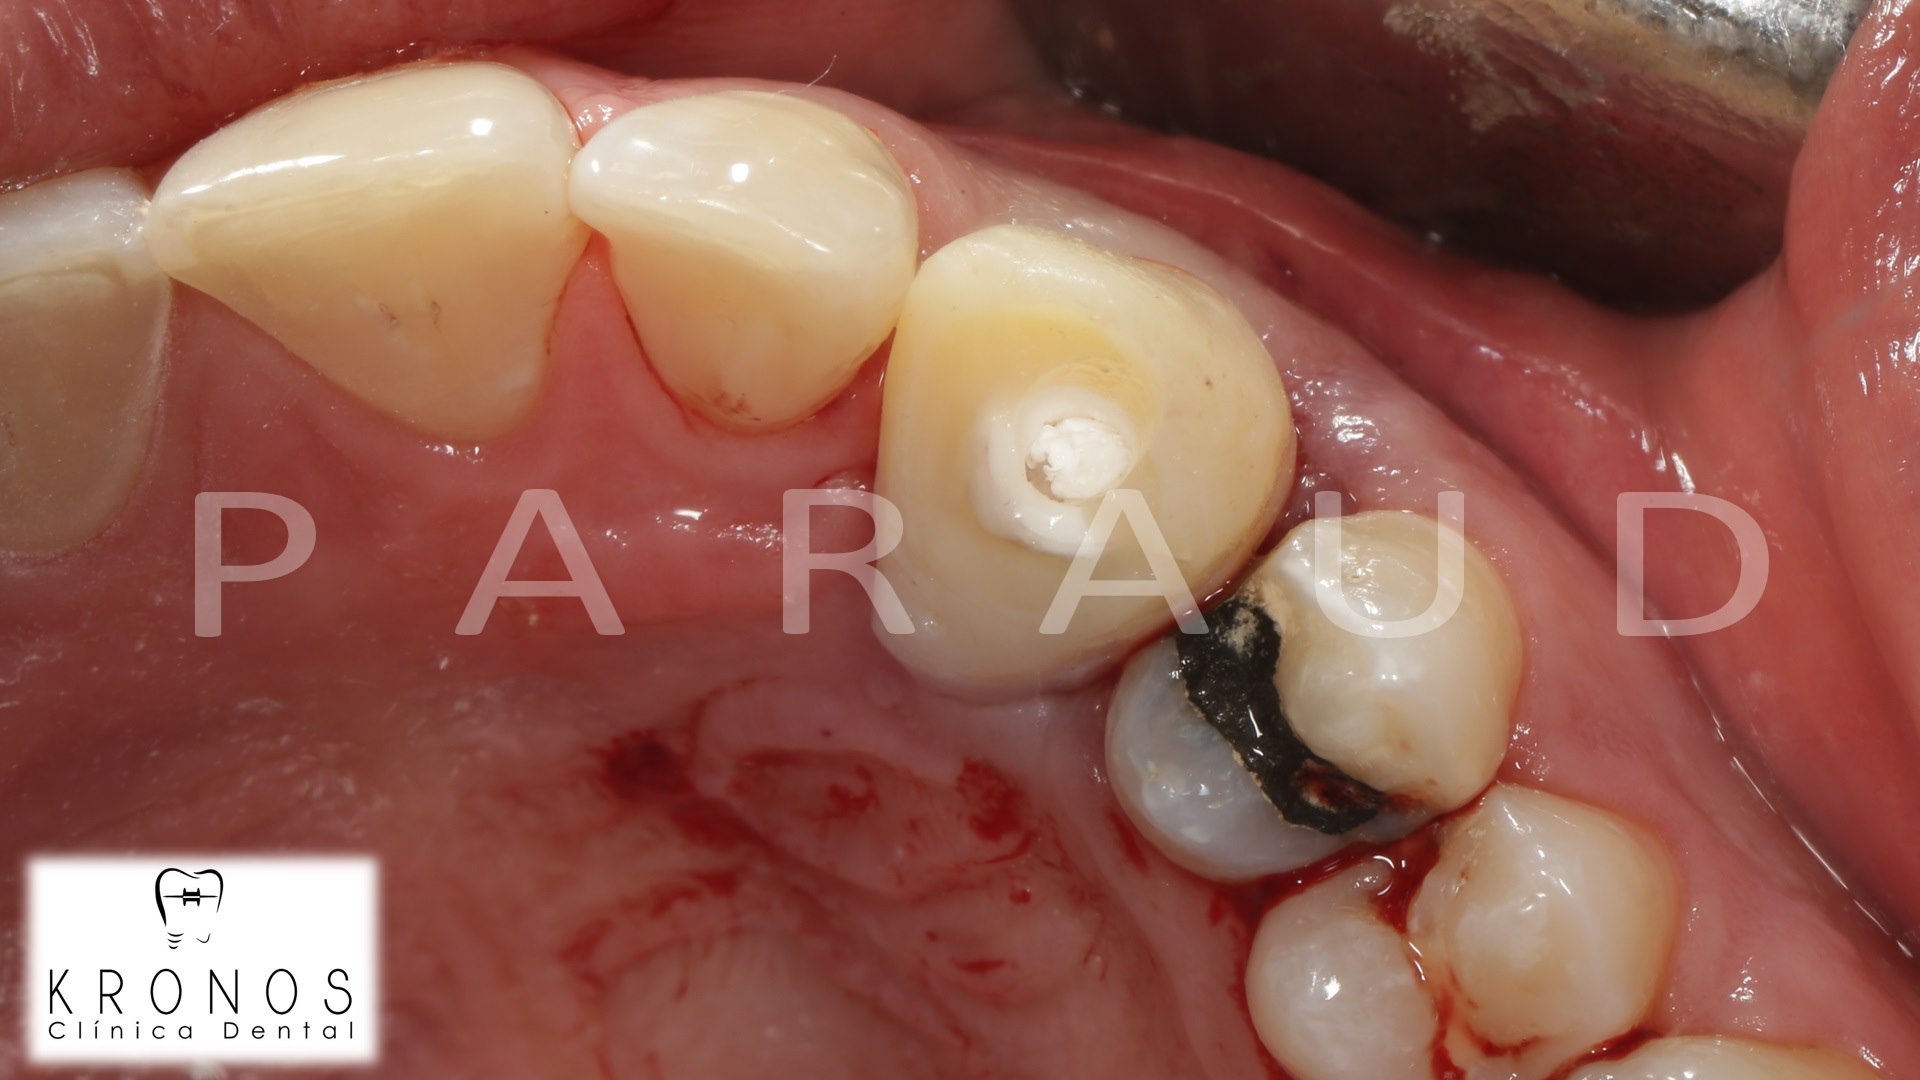

Clinical case: Extraction, immediate implant placement, & provisionalization

- Courtesy of Dr. Iulian Filipov, Romania -

AnyRidge, R2GATE, guided surgery, immediate placement, immediate provisionalization, initial stability, Dr. Iulian Filipov, #25, maxillary posterior, immediate loading, Mega ISQ

AnyRidge implant system, R2GATE, MEGA ISQ, Digital prosthesis

“Patient’s smile was recovered on the day of surgery

with reliable & highly-aesthetic results using AnyRidge & R2GATE. ”